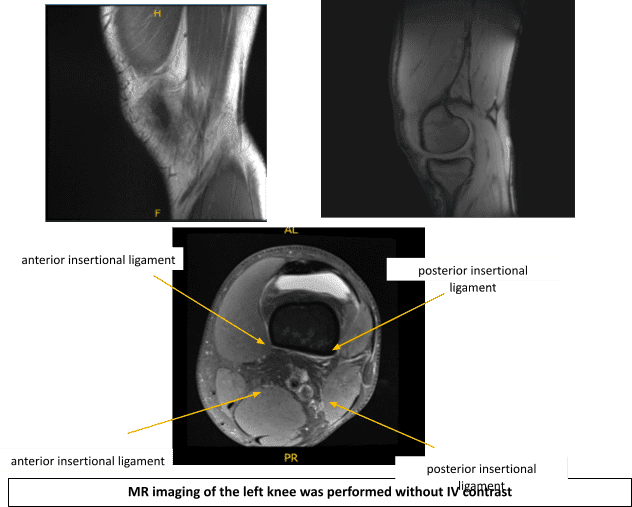

An MRI was performed. There is a complex tear of the lateral meniscus with displacement of the majority of the posterior horn and body-posterior junction displaced anteromedially, immediately posterior to the anterior horn.

There is intra-meniscal cyst formation within the displaced meniscus as well as within the native anterior horn with a cluster of parameniscal cyst seen anteriorly measuring up to 1.2 x 1.4 x 1.5 cm (craniocaudal x anteroposterior x transverse dimension). There is full-thickness cartilage loss overlying the central weight bearing aspect of the lateral femoral condyle spanning approximately 1.4 x 0.5 cm with a nondisplaced delamination flap medially.